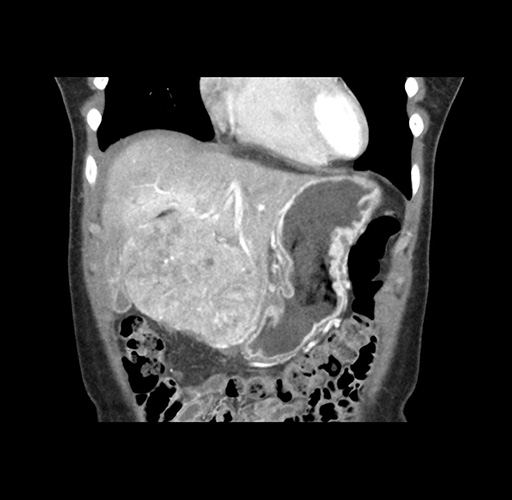

Imaging Analysis

Look through the patient's CT scan to identify any areas of concern for the necessary procedure.

Based on your CT findings, which issue(s) would give reason for "planned slowing down moment(s)" in this case?

Considering a standard left lateral sectionectomy procedure, what step(s) of the operation would you do differently in this case ?